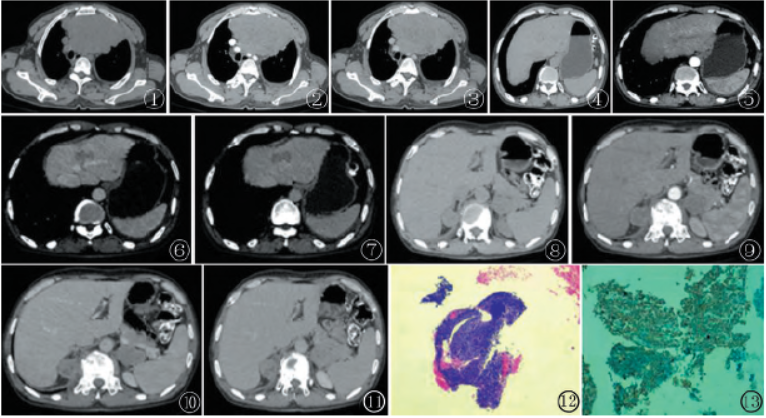

患者 男,56岁。因“1月前无明显诱因腰部疼痛”就诊。查体无异常。胸部CT显示前纵隔内见不规则软组织肿块影,边界欠清,内密度欠均匀,呈分叶状,平扫CT值约40 HU(图1)。增强扫描后肿块呈不均匀强化,动静脉期CT值分别约50 HU、58 HU(图2,3)。诊断前纵隔占位性病变:考虑恶性肿瘤性病变,淋巴瘤可能性大。全腹CT显示肝内多处斑片状稍低密度影,边界欠清,平扫CT值约38 HU(图4)。

增强扫描动脉期呈轻-中度不均匀强化,门静脉期及静脉期呈持续性强化(图5~7)。双侧肾上腺区见多个团块影,密度不均,边界较清,平扫CT值约32 HU(图8)。增强扫描呈轻度持续性强化,病变局部与肝右缘分界不清(图9~11)。

全腹CT诊断肝内及双侧肾上腺区多发占位性病变:考虑多发转移瘤。行CT引导下前纵隔穿刺活检,病理报告(前纵隔)梭形细胞肿瘤,符合恶性黑色素瘤(图12,13)。免疫组化:CD117(+),CD5(-),CK(-),CK5/6(-),CK7(-),P63(-),TTF-1(-),Ki-67(+10~20%),Vimentin(-),Mela-n-A(+),S-100(-),HMB-45(+)。

图1胸部CT平扫

显示前上纵隔内不规则软组织肿块影,其内密度欠均匀;图2,3胸部CT增强显示前上纵隔肿块呈不均匀轻中度强化;图4腹部CT平扫显示肝脏多发片状低密度影,边界欠清;图5~7CT增强显示肝脏病灶呈不均匀持续性强化;图8腹部CT平扫显示双侧肾脏团块状低密度影,周围脂肪间隙模糊;图9~11CT增强显示双侧肾脏病灶呈不均匀持续性强化;图12病理HE染色显示细胞有异型性,部分可见黑色素颗粒(HE,×100);图13免疫组化显示Ki-67(+10~20%),HMB-45(+)